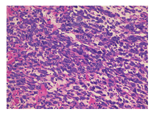

为明确病变性质,患者行18F-脱氧葡萄糖(fluorodeoxyglucose, FDG)PET/CT(美国GE Discovery STE)显像(图1C)示:肿块实性部分18F-FDG摄取明显增高,最大标准摄取值(maximum standardized uptake value, SUVmax)为16.8,间质部分摄取相对不高,SUVmax为4.0,考虑乙状结肠间质瘤。电子结肠镜检查:进镜20 cm可见一巨大黏膜隆起,表面粗糙,活组织检查弹性可,致肠腔稍狭窄。肿块切除术术中乙状结肠见一浸润性肿块,大小约10 cm×15 cm,明显浸出浆膜层,侵犯左侧腹壁。大体检查:送检肠管1段,肠管长18 cm,周径6~9 cm,黏膜表面尚光滑,距切端3 cm乙状结肠见一巨大团块状肿物,大小约14 cm×7 cm×6 cm,位于黏膜下至浆膜外,切面灰白色,质韧,局灶出血,见暗红色。病理检查(图2):光学显微镜下示肠壁间及浆膜面见肿瘤细胞弥漫片状分布,部分漂浮于黏液间质中。瘤细胞形态卵圆形,部分呈上皮样。胞质丰富、嗜双色,核大,空泡样,核仁及核分裂象易见。间质中大量炎性细胞浸润,以中性粒细胞为主。免疫组织化学检查示:间变性淋巴瘤激酶(anaplastic lymphoma kinase, ALK)(P80)(+++)、ALK(D5F3)(+++)、结蛋白(desmin;+)、CD30(+)、细胞增殖核抗原Ki-67(30%)、CD34(血管+)、平滑肌肌动蛋白(smooth muscle actin, SMA;-)。最终诊断:乙状结肠上皮样炎性肌纤维母细胞肉瘤(epithelioid inflammatory myofibroblastic sarcoma, EIMS)。